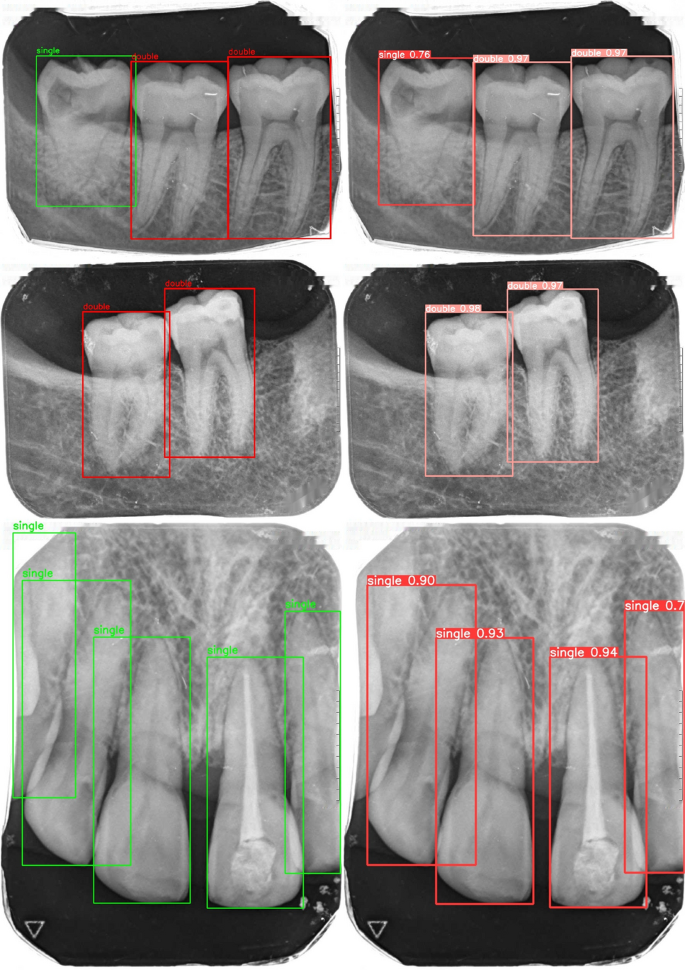

To assess whether these differences were statistically significant, we performed paired hypothesis testing on the test set using per-image Average Precision (AP) \(_{50{:}95}\) values, with YOLOv8x as the reference model. The resulting p-values were \(3.91 \times 10^{-35}\) for YOLOv8n and \(4.4 \times 10^{-51}\) for YOLOv9e, indicating statistically significant performance differences relative to YOLOv8x. Figure 7 shows example predictions of YOLOv8x compared with ground truth annotations.

Comparison of ground truth (left) and predicted (right) tooth detection.

Comparison of ground truth and predicted key points for tooth analysis: a cemento-enamel junction (CEJ) points; b alveolar bone level and tooth intersection points; c apex points. Blue points indicate ground truth, red points indicate predictions.